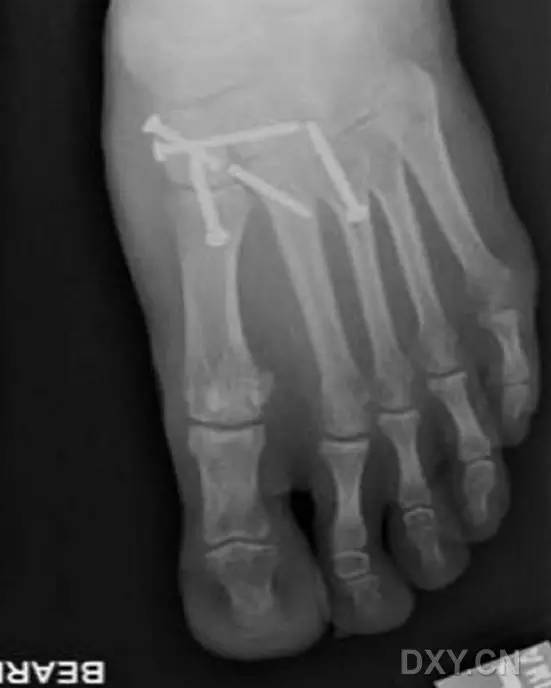

完成术区暴露和维持复位后,在 X 线透视下,自足底方向经第 2 跖骨基底背外侧向内侧楔骨置入导针,采用空心钻经导针钻孔,然后将一枚 4.0 - 5.0 mm 直径适当长度的半螺纹空心螺钉经导针置入(图 4)。

图 4. 术中 X 线透视下,经第 2 跖骨基底背外侧向内侧楔骨置入 Lisfranc 螺钉